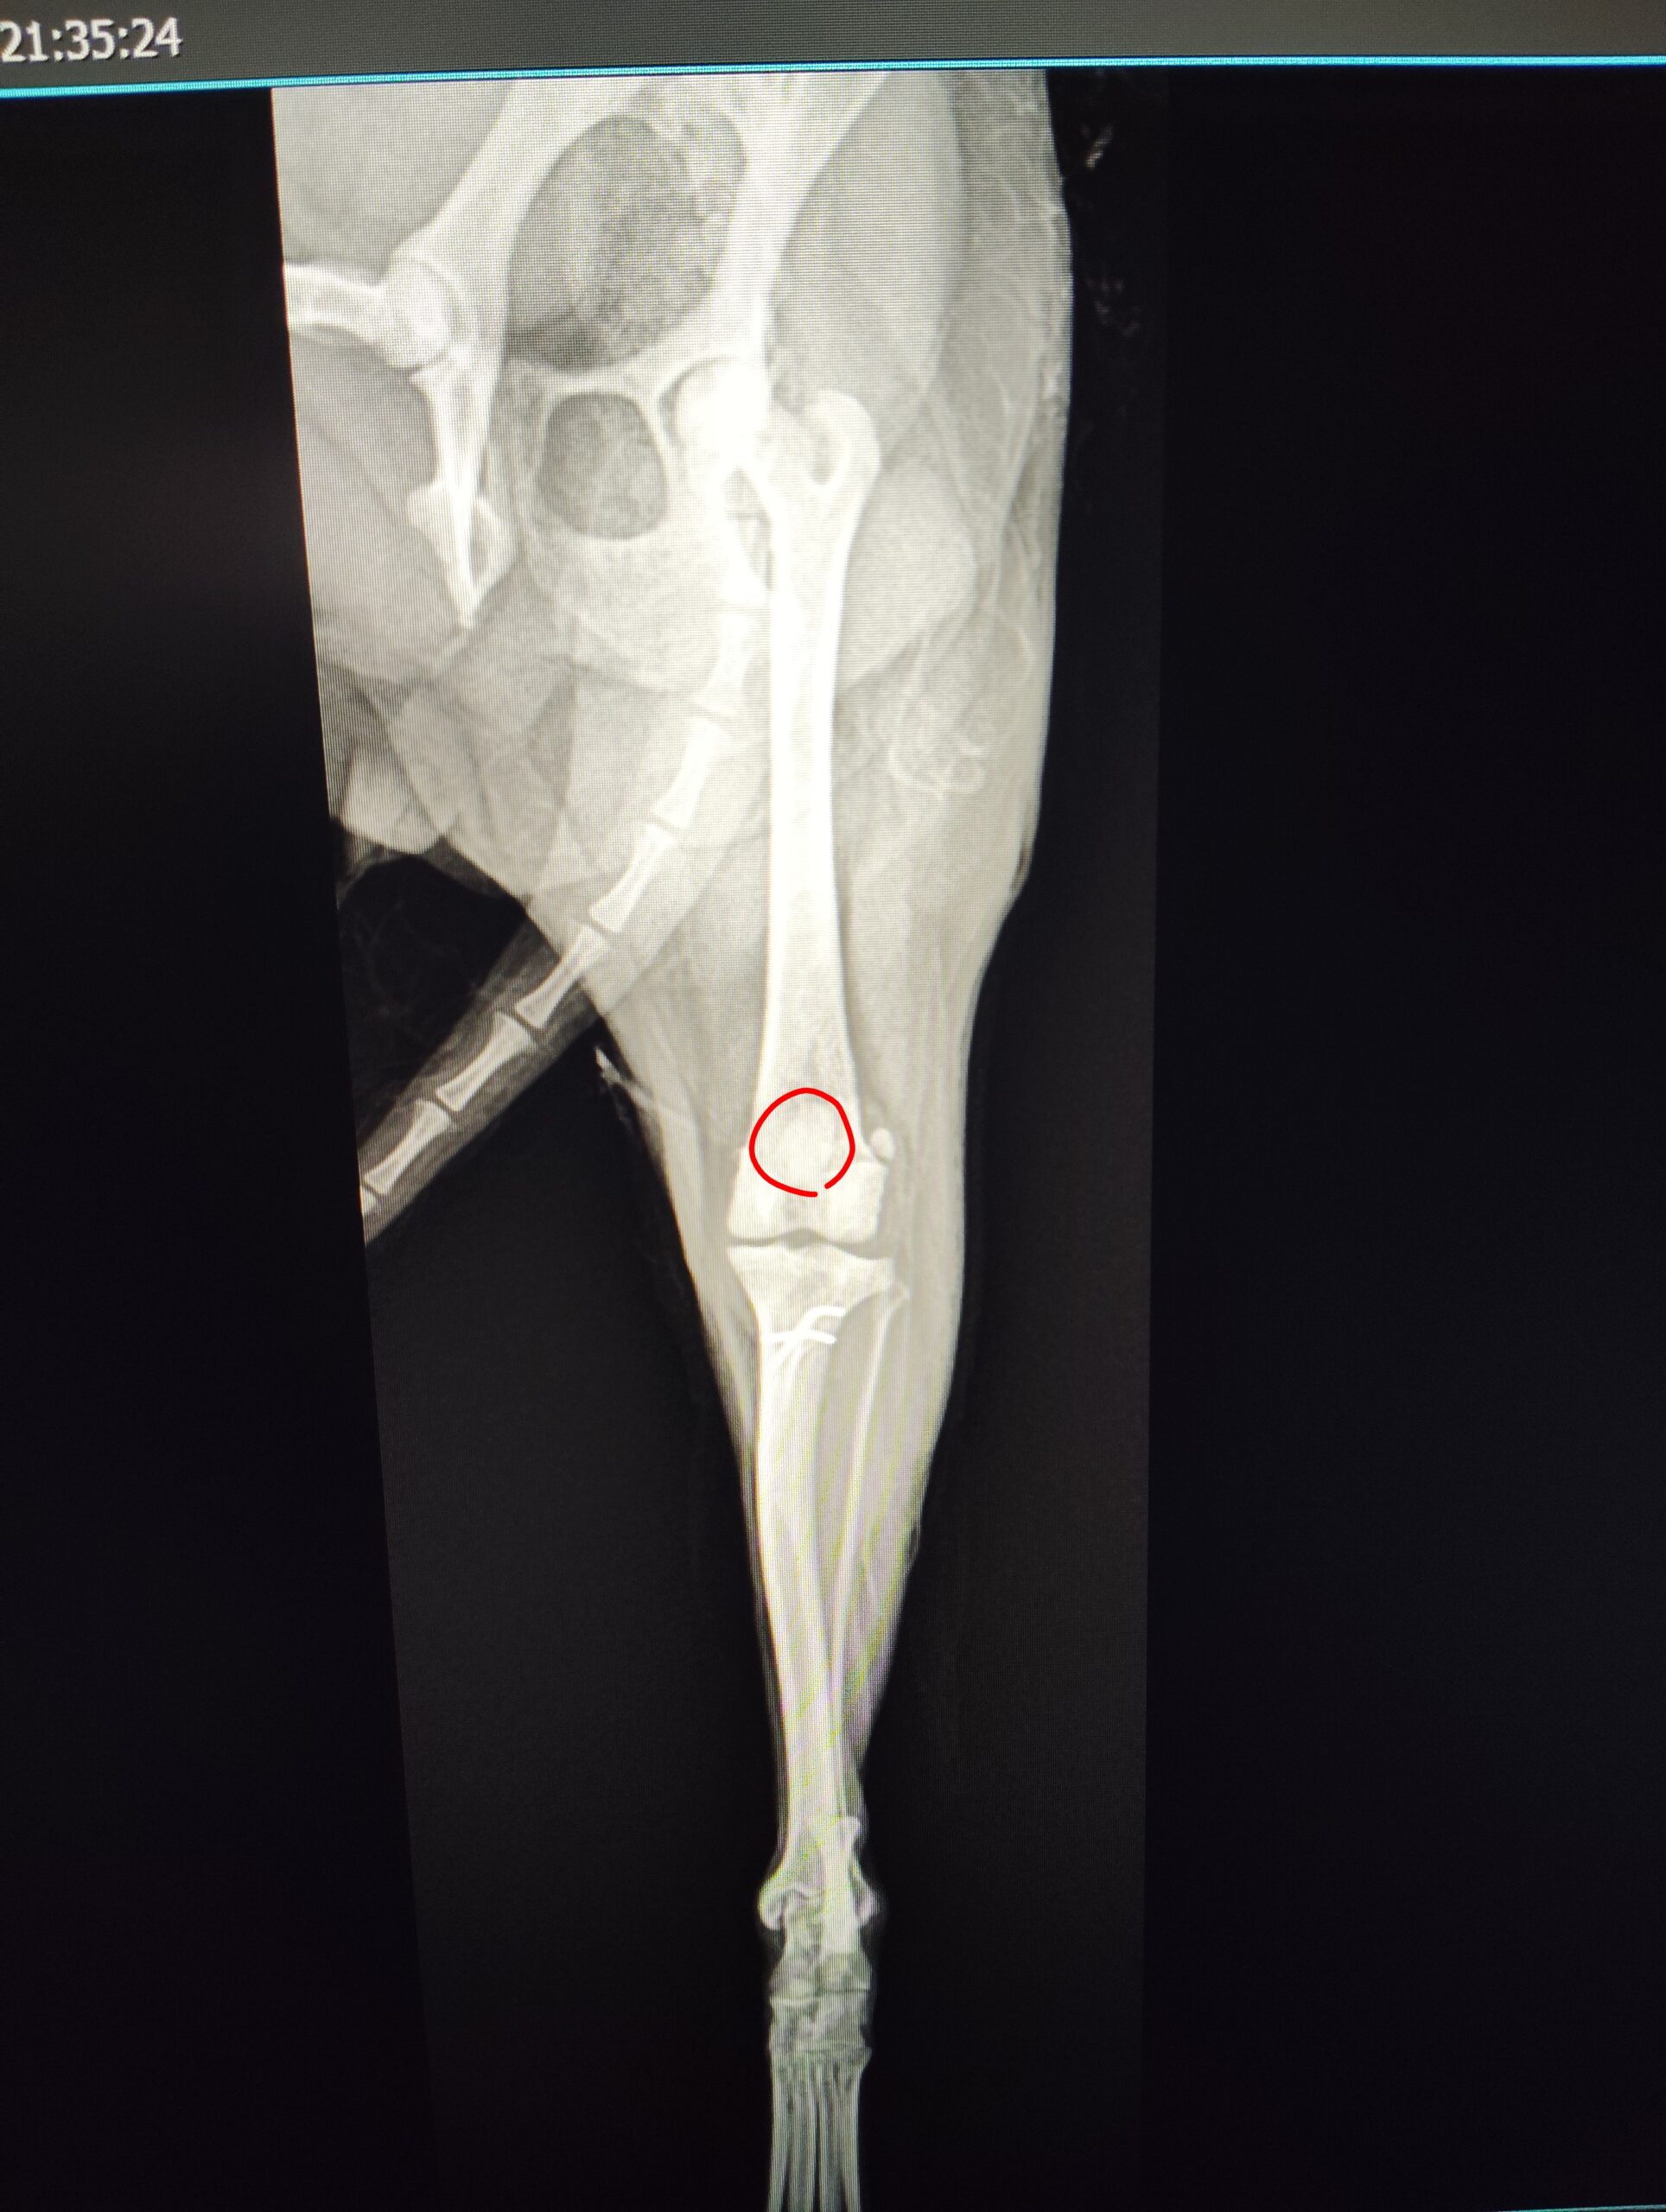

- レントゲン検査にて結腸拡張(便塊の貯留)を確認